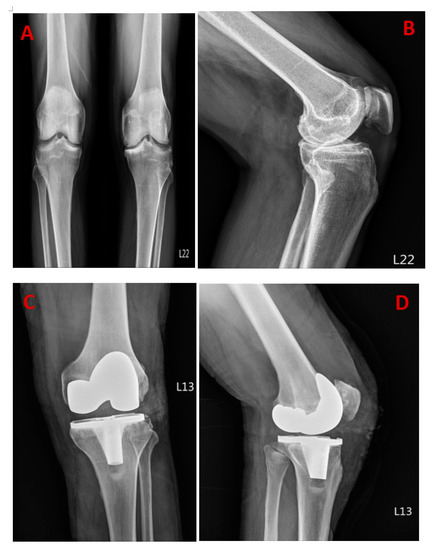

Figure 1A shows the initial radiography revealing bilateral knee Kellgren–Lawrence grade IV osteoarthritic change, with Figure 1B showing the medial joint space narrowing mostly on the right knee. Figure 1C,D shows the successful total knee replacement (TKR) on the right knee. A 59-year-old man has a history of hypertension for over ten years and receives regular medication control for hypertriglyceridemia and depression. His surgical history includes laparotomy surgery for perforated peptic ulcers and an appendectomy. He suffered from bilateral knee pain for years, especially in his right knee. The knee pain aggravated while walking and climbing up the stairs, and therefore, he was seeking medical help. Once TKR was successful, two days after his operation, a sudden fever of 40.5 Celsius degrees developed, accompanied by nausea, vomiting, and abdominal distention. Laboratory data revealed leukocytosis (white blood cells: 12.81/uL), elevated C-reactive protein (41.22 mg/dL), and elevated procalcitonin (5.20 ng/mL). Further workup was arranged for identifying the possible infection, focusing on the gastrointestinal (GI) tract. His esophagogastroduodenoscopy examination only showed reflux esophagitis and superficial gastritis, and his colonoscopy reported no positive findings. The abdominal ultrasound also did not identify any abdominal site of infection. However, persistent fever was still noted. The antibiotics were customized by the infection specialist. Necrotizing fasciitis (NF) is a severe infection of the subcutaneous tissue, characterized by the necrosis of the subcutaneous tissues and fascia, and is usually results from a group A beta-hemolytic streptococcal infection or polymicrobial synergistic infection [1]. Mortality from this infection is significant if left untreated or if treatment is delayed. Early diagnosis and definitive management are paramount because of the rapidly progressing nature of the infection [2,3,4,5]. The incidence of this disease has increased about five-fold during the last decade, which can be partly due to an increase in the number of immune-deficient patients, and may even be due to frequent reports during recent years. Mortality rates range from 30% to 90%, according to the recently published book [6]. Gastrointestinal symptoms are also one of the possible predictors of severe outcomes of invasive group A streptococcal infections, as reported in a 2010 study [7]. As a result of the high mortality rate in patients suffering from this disease and the lack of adequate research in this field, we wanted to record the complications and symptoms that have occurred along with several examinations and tests that we have analyzed up until the removal of implements, and the acceptation of flap reconstruction.

Figure 1. Initial radiography images before total knee replacement (A,B) with successful post-surgery radiography (C,D).